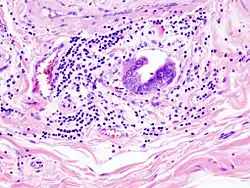

- Incidentally discovered gallbladder cancer (adenocarcinoma) following a cholecystectomy.

- Gallbladder adenocarcinoma histopathology